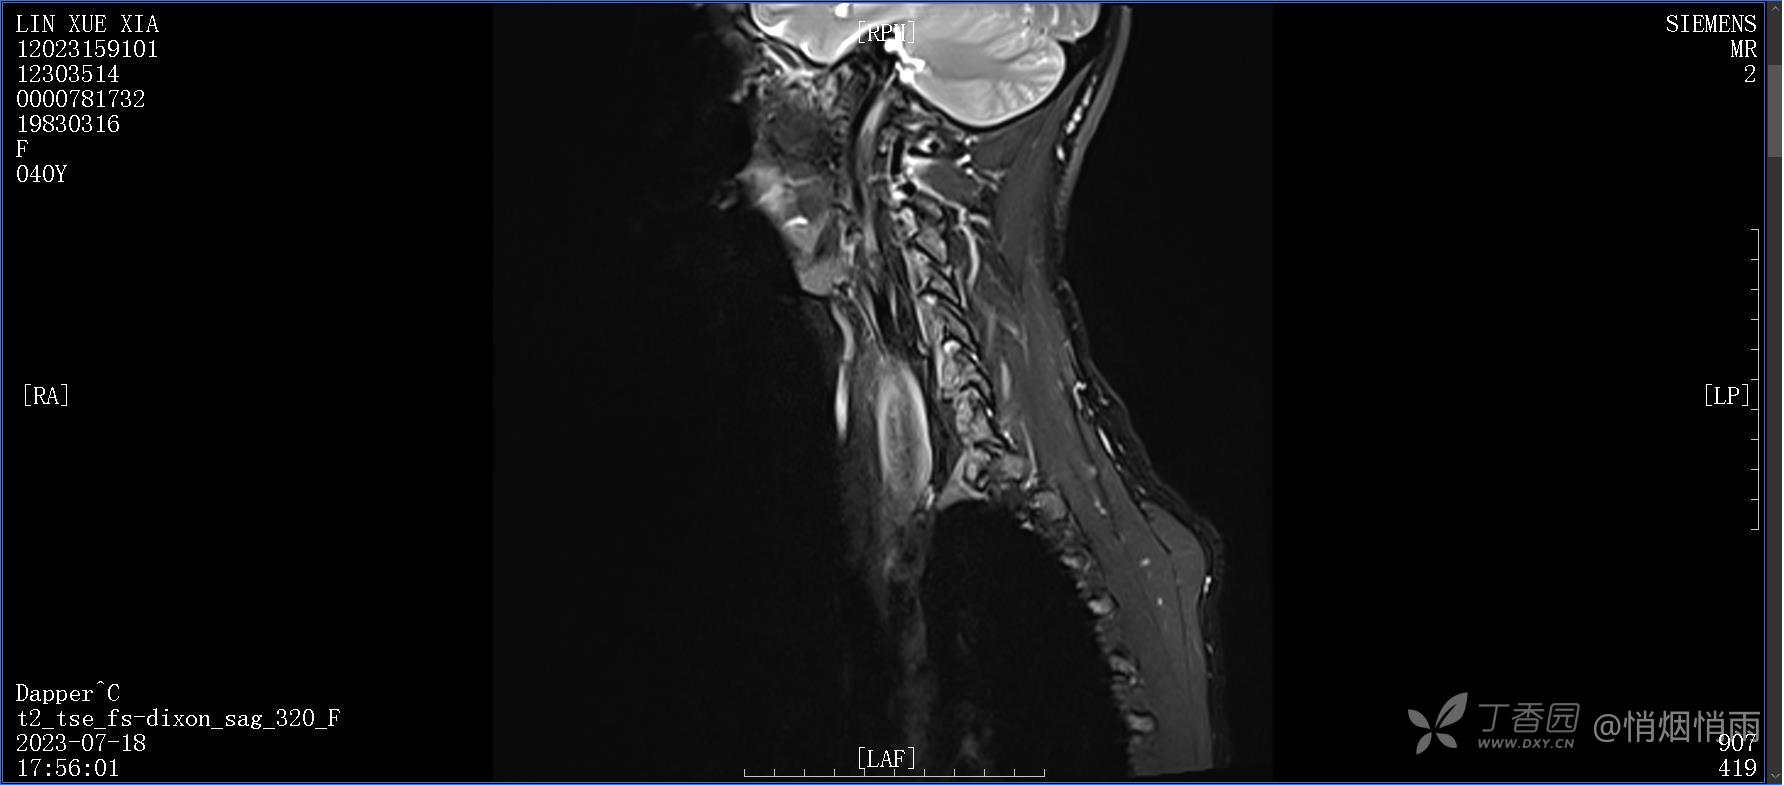

NeurothinkerZ 推荐患者女性,40岁,因右肩背部疼痛班活动受限4日余入院(2023-07-17)。

病史:入院前4天无明显诱因突然感右肩背疼痛伴随活动受限,自行口服依托考昔、艾瑞昔布等药物治疗,院外应用肩关节局部手法按摩等,均无明显改善。外院门诊诊为颈椎病。自诉既往多次“胸椎小关节紊乱”于当地诊所行手法按摩,治疗后好转,否认慢性疾病病史、外伤史、手术史,诉青霉素过敏,无其他药物食物过敏史,否认吸烟史、饮酒史,月经正常,经量正常。

目前的诊断,暂时依据辅助检查诊为肩袖损伤,但是患者疼痛的性质和特点,却不是单纯的肩袖损伤所致。考虑过胸廓出口综合征,但是该疾病会出现肩胛区的疼痛吗?(由于考虑到费用的问题,没再进行下一步的检查)带状疱疹会有如此的症状吗?